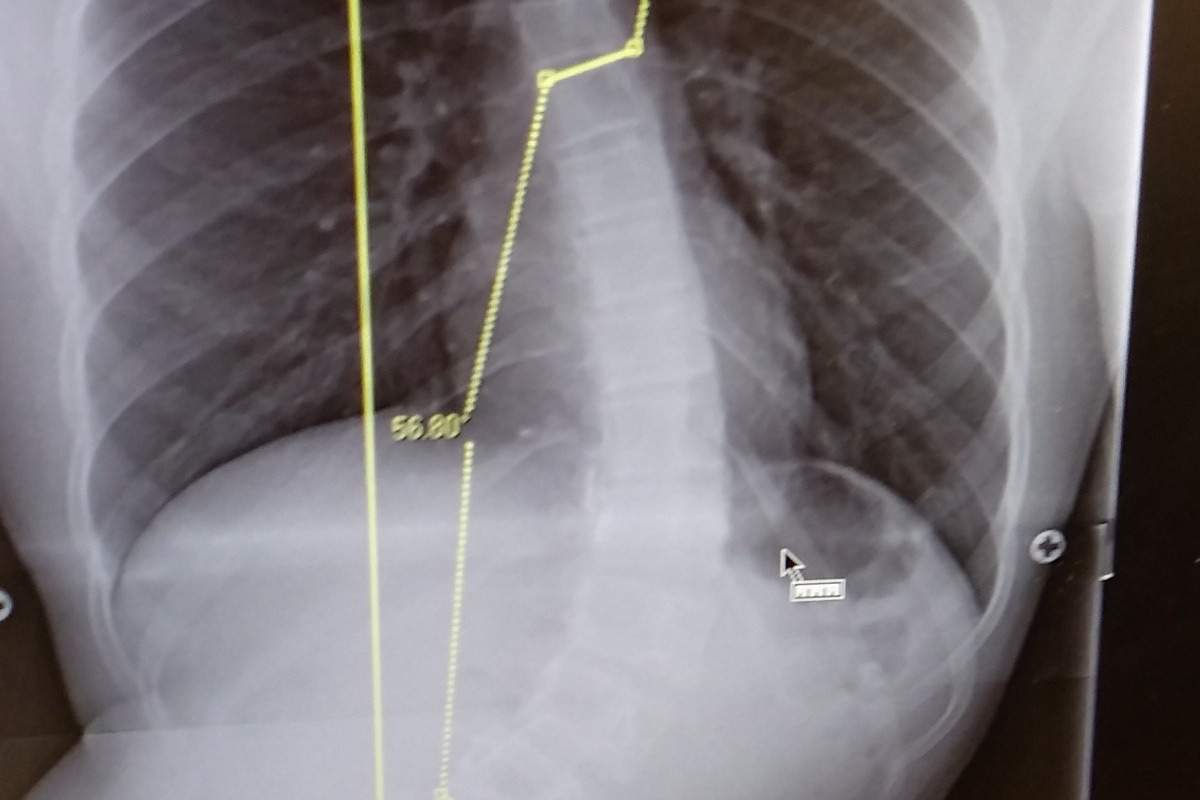

Proud single mother who has an amazing 16 year old son that was recently diagnosed with Scoliosis and is needs immediate Idiopathic Surgery before organ failure onsets. We have an amazing surgeon at Gillette's Children's Hospital and spinal surgery is taking place on June 14th 2021. There will be a 3-4 day stay at the hospital and 4 weeks post surgery he will have to have 4-6 weeks of rehabilitation therapy 2 times a week. They are inserting a rod from right below his neck to right above his pelvic bone. Many prayers and well wishes are so much appreciated! Thank you in advance for anything you are able to contribute, I am very modest in my ask and will not know fully out of pocket it will end up being. An important message is he .. Is going to have an Iron Man back. (His fav Marvel Hero)